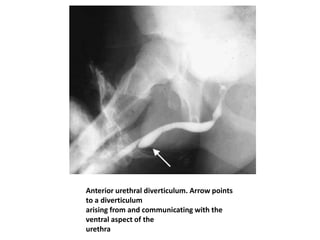

Anterior urethral diverticulum. Arrow points

to a diverticulum

arising from and communicating with the

ventral aspect of the

urethra

Urethral Diverticula • Anteriorurethral diverticulum, although uncommon, is the second most common cause of congenital urethral obstruction in boys. • A diverticulum of the anterior urethra develops on the ventral surface of the penile urethra as a result of either incomplete development of the corpus spongiosum focally or incomplete fusion of a segment of the urethral plate. • A lip of tissue may be seen around the diverticulum. As the diverticulum distends, the lip of tissue is pressed against the urethral wall and results in a valve like obstruction .

• 77.

Anterior urethral diverticulum.Arrow points to a diverticulum arising from and communicating with the ventral aspect of the urethra

• Most childrenare diagnosed in infancy with dribbling-type micturation or infection. • The dribbling may be due to emptying of the diverticulum or to overflow incontinence. If the obstruction is distal, ballooning of the urethra may occur with voiding. VCUG is the key to diagnosis. During VCUG, the typical saccular diverticulum of the anterior urethra fills with contrast material and appears as an oval structure on the ventral aspect of the anterior urethra